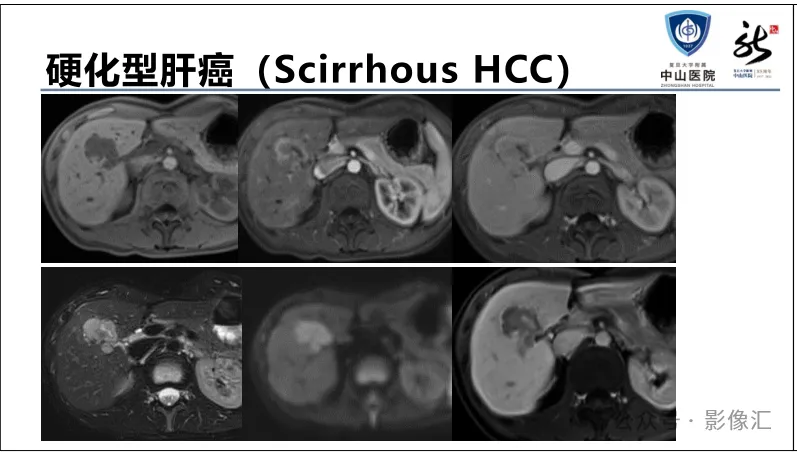

>【精品课件】如何正确判读肝胆特异性对比剂增强图像?

肝胆特异性对比剂增强肝胆图像判读方法与策略,课件来源于网络,作者复旦大学附属中山医院放射科饶圣祥教授。